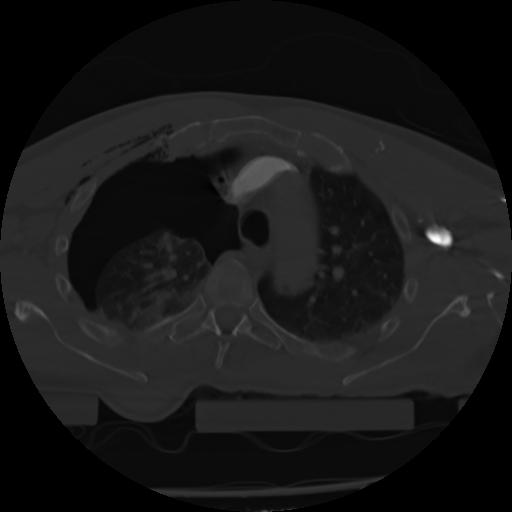

21 ANGIO,CE,Axial,3.0,ANGIO,,